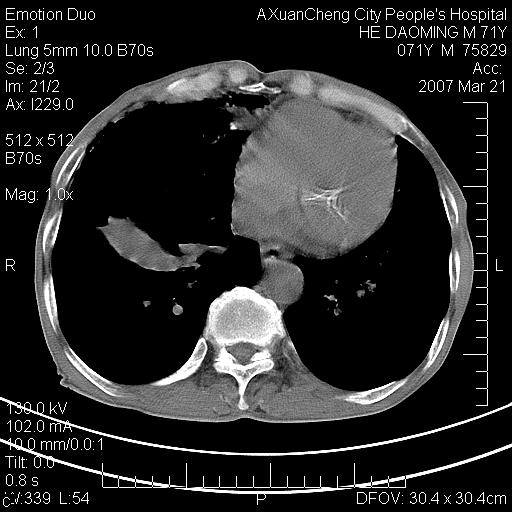

标题: CT7269:[原创] 咳嗽,咳痰,大家讨论右肺病变的部位 [打印本页]

标题: CT7269:[原创] 咳嗽,咳痰,大家讨论右肺病变的部位

1.慢支肺气肿 肺心病 肺大泡;2.叶间裂积液,前胸膜粘连

右侧相当于叶间软组织样密度ct值约50hu,请大家讨论是什么性者病变

右下肺大囊肿伴感染.肺气肿,肺大泡.

考虑:慢性支气管炎合并全小型肺气肿、肺大泡、间质纤维化、感染,右斜裂积液。

考虑慢支,肺气肿,肺大泡,间质纤维化;右侧斜裂液气胸考虑(可能因为肺大泡破裂破入斜裂所致).

考虑病变以右上中肺多发肺大泡为主并感染。请结合临床考虑慢支肺气肿,肺心病。

1双肺慢性支气管炎并全小叶型肺气肿肺大泡2间质性纤维化3右侧斜裂积液

考虑:慢性支气管炎合并右侧全小型肺气肿、肺大泡并感染、双肺间质纤维化,右斜裂积液。

考虑:慢性支气管炎合并右侧全小型肺气肿、肺大泡并感染、双肺间质纤维化,右斜裂积液。右侧斜裂液气胸考虑(可能因为肺大泡破裂破入斜裂所致).